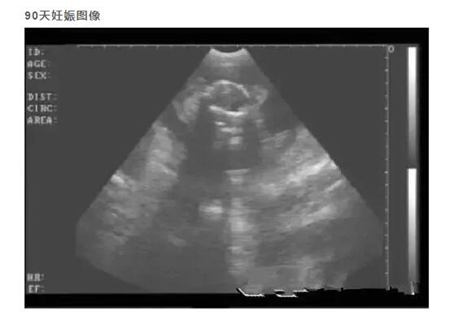

20天孕期左右的母猪,即可进行B超测孕,但由于羊水太少,图像不好判断,准确度也会因检测人员经验因素有所影响,容易造成误判,而且检查时间长,耗费人力。

45天孕期后的母猪测孕,羊水开始吸收并减少,小猪开始成型,图像复杂同样不好判断。同时,母猪的情期平均是21天,如果不能在第21天至42天之内确定是否怀孕,那意味着猪场又要再养一个周期才能配种,造成极大的浪费。